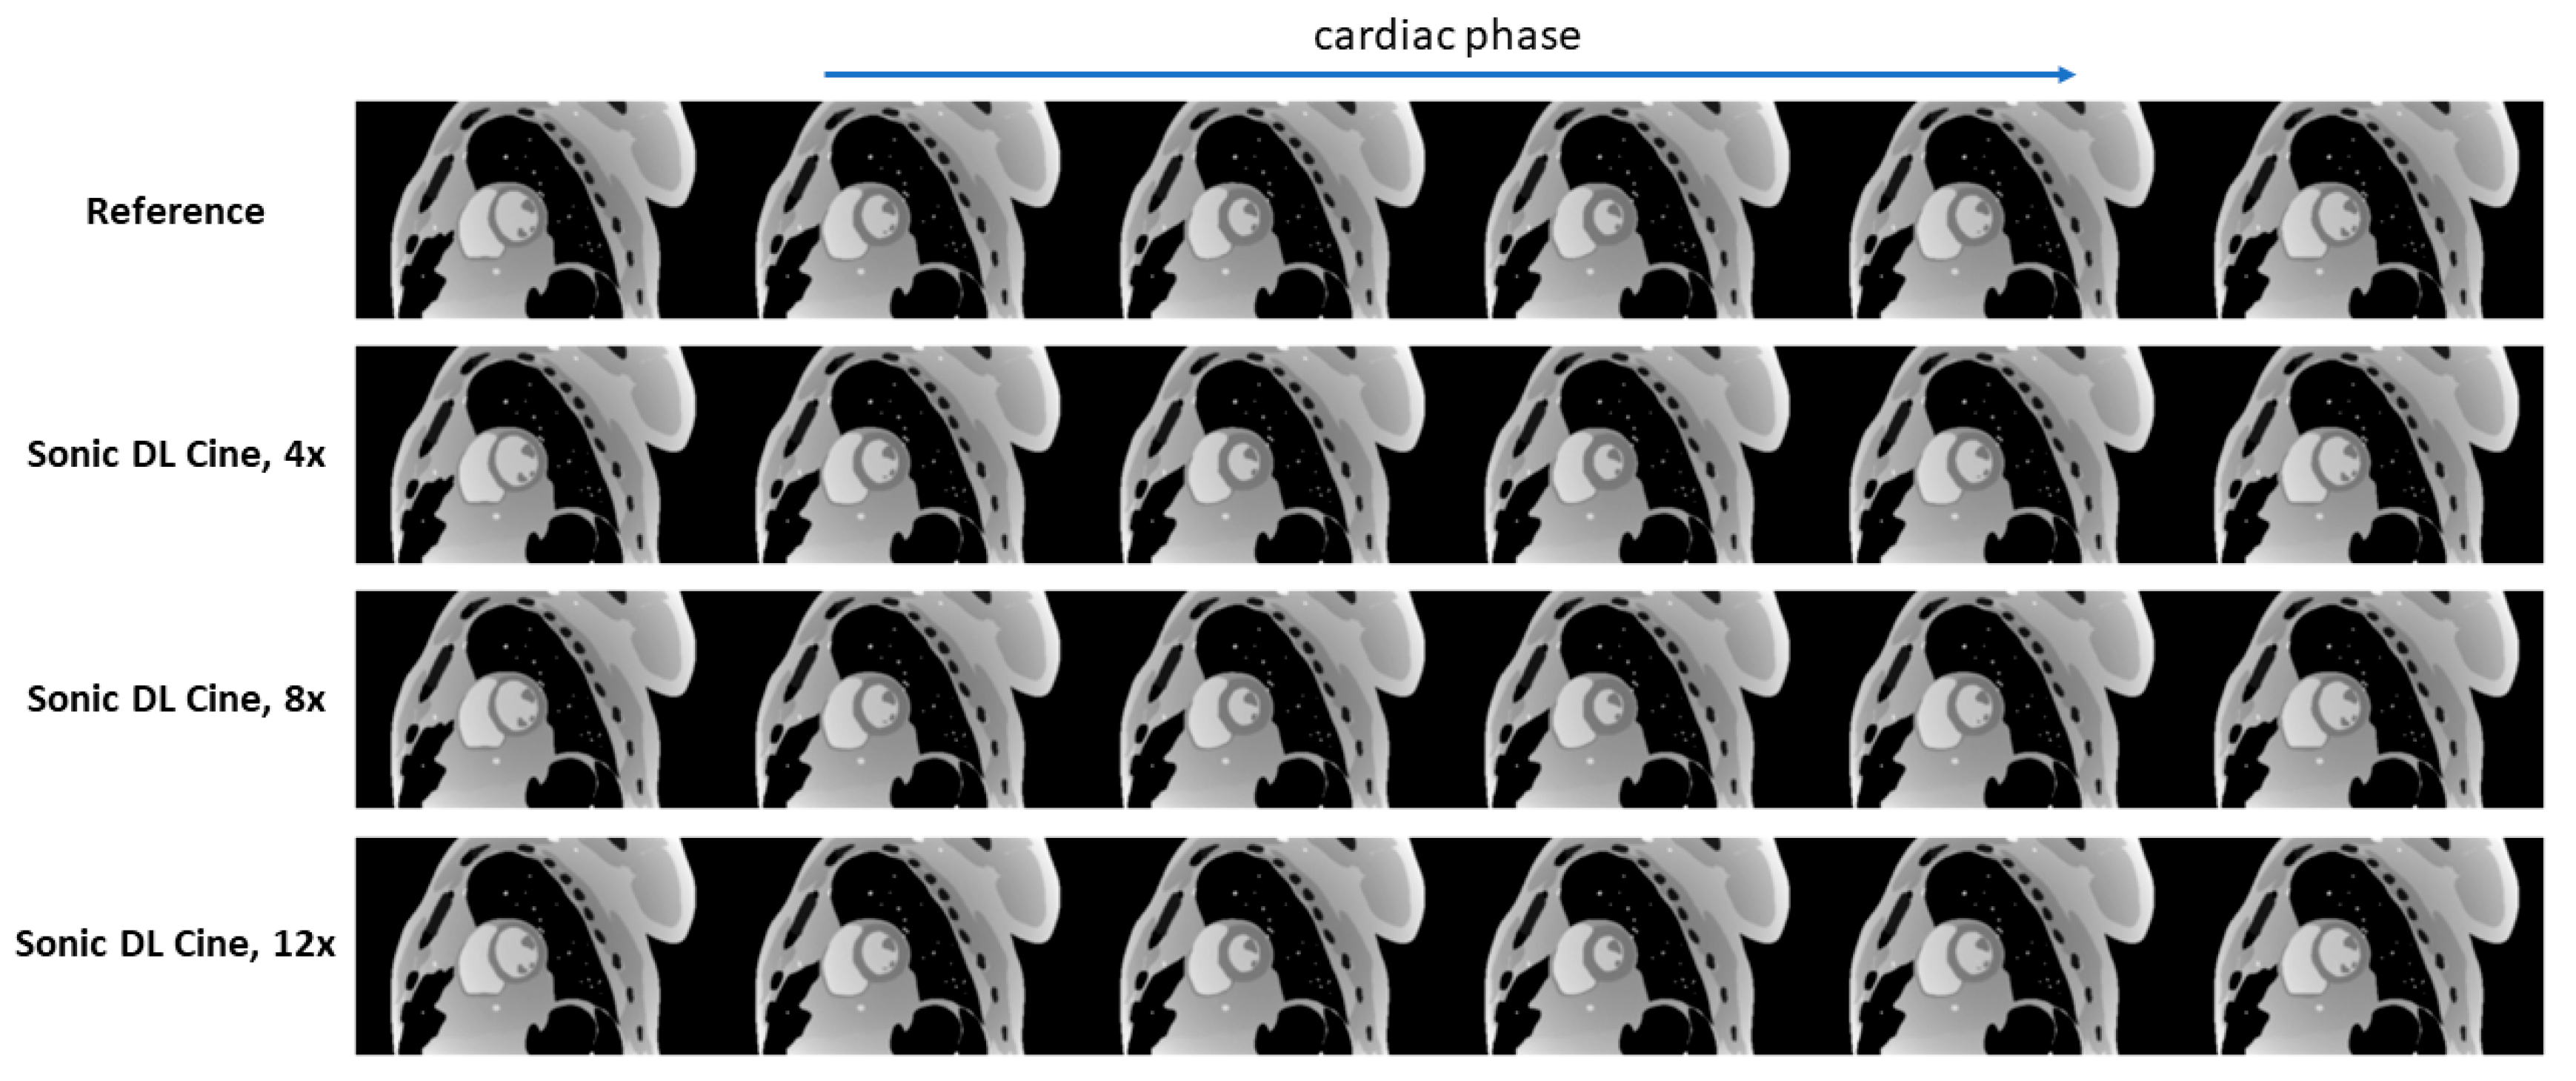

| Acceleration Factor | PSNR | SSIM | RMSE | MAE |

|---|---|---|---|---|

| 4 | 46.65 | 0.95 | 0.0047 | 0.0037 |

| 8 | 45.48 | 0.94 | 0.0053 | 0.0042 |

| 12 | 44.76 | 0.94 | 0.0058 | 0.0045 |